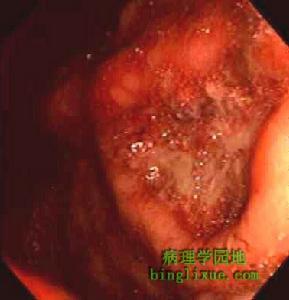

(1)胃鏡。

1.胃鏡檢查是診斷該病的最有效手段,列為首選,胃鏡應在出血24h內或在出血即時進行。胃鏡下可見食管與胃交界處或食管遠端、賁門黏膜的縱行撕裂,撕裂多為單發,少數為多發,裂傷一般長3~20mm,寬2~3mm。胃鏡下可將裂傷出血分為5類:①活動性動脈性噴血;②活動性血管滲血;③可見血管顯露;④裂傷處黏附有新鮮血痂;⑤單純性裂傷。